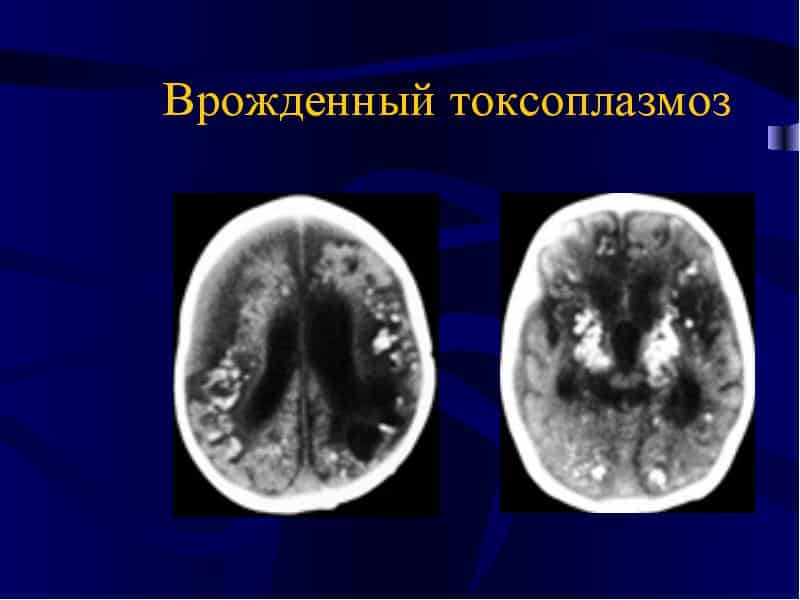

Врожденный токсоплазмоз, лечение которого представляет собой серьезную проблему, возникает у новорожденных, если мать была инфицирована. В этом случае острая стадия заболевания развивается внутриутробно, и ребенок рождается с энцефалитом. Такие дети могут отставать в умственном развитии и проявлять другие признаки токсоплазмоза.

- МРТ головного мозга рекомендуется при подозрении на врожденную форму заболевания.